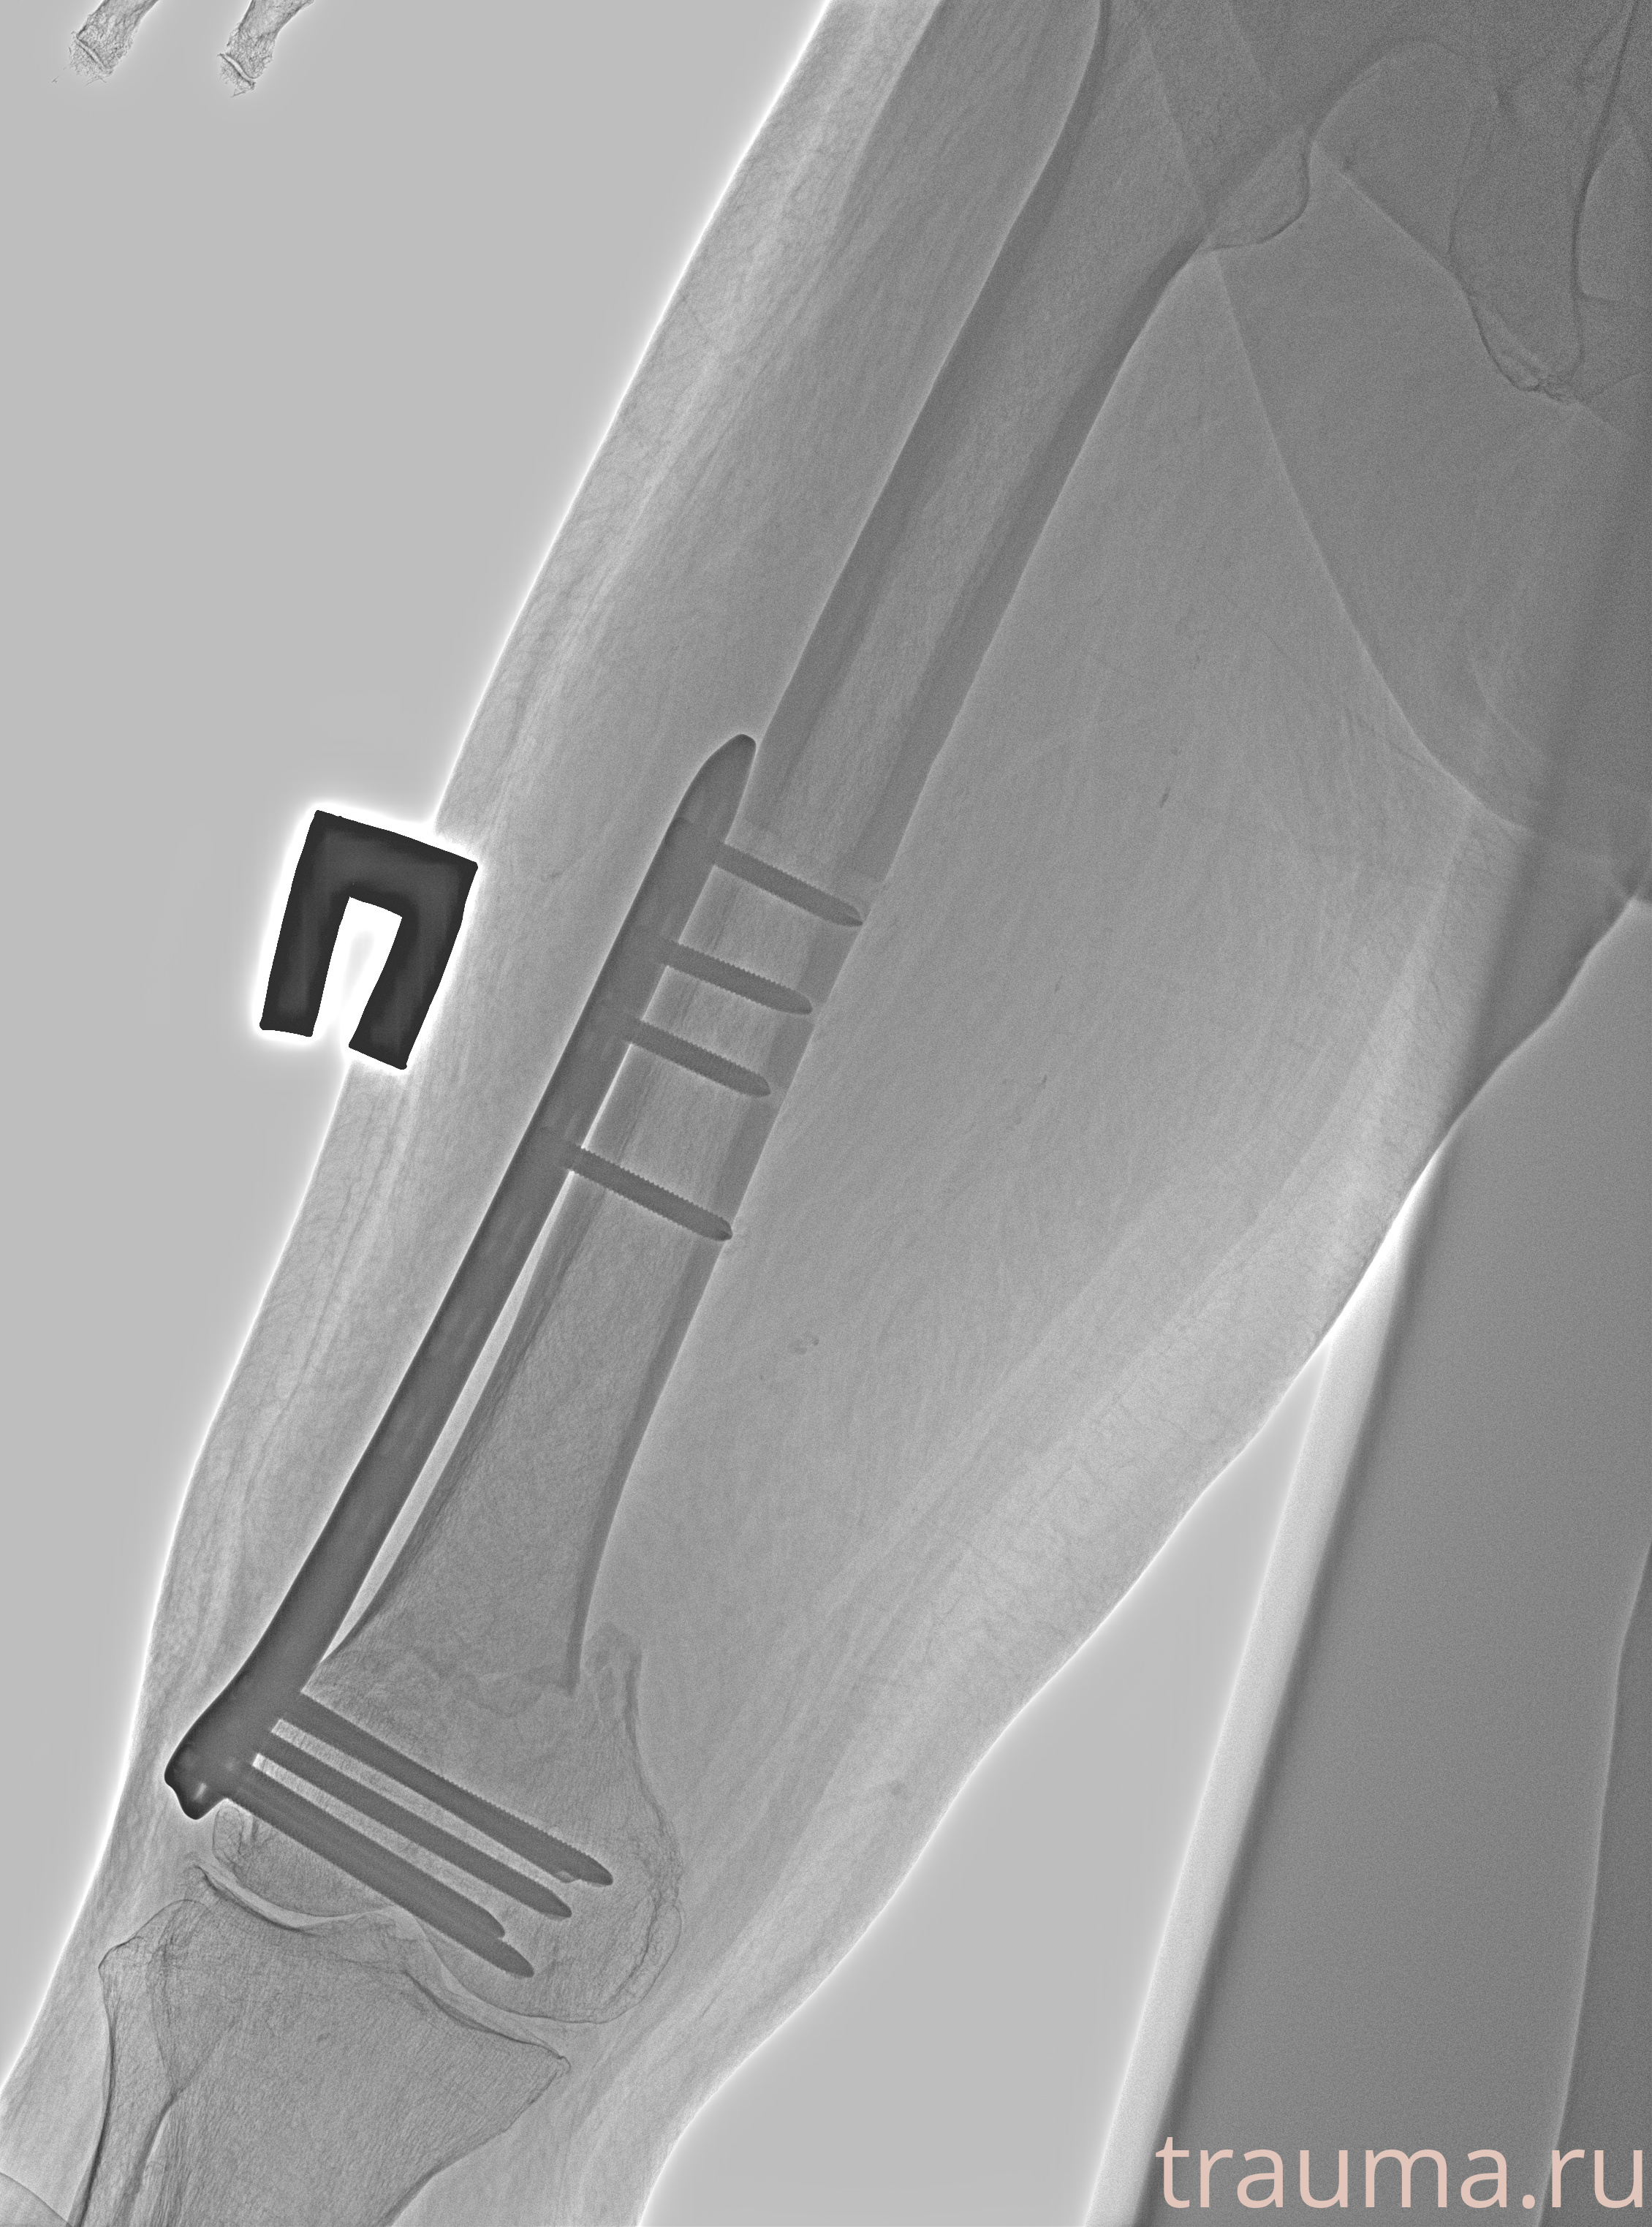

Рентгенограммы

Рентген на дому: по вашему адресу приезжает врач-рентгенолог, травматолог-ортопед с мобильным рентгеновским аппаратом, проводит диагностику травмы или заболевания, делает необходимые рентгенограммы, дает рекомендации по дальнейшему лечению. Получить качественные снимки в домашних условиях возможно благодаря уникальной методике, разработанной МосРентген Центром для института  Склифосовского